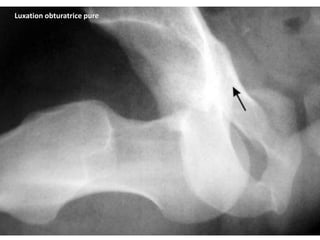

La luxation antérieure (rare 25%):

Elle peut être obturatrice (15 %) ou pubienne

(10 %).

Luxation obturatrice pure